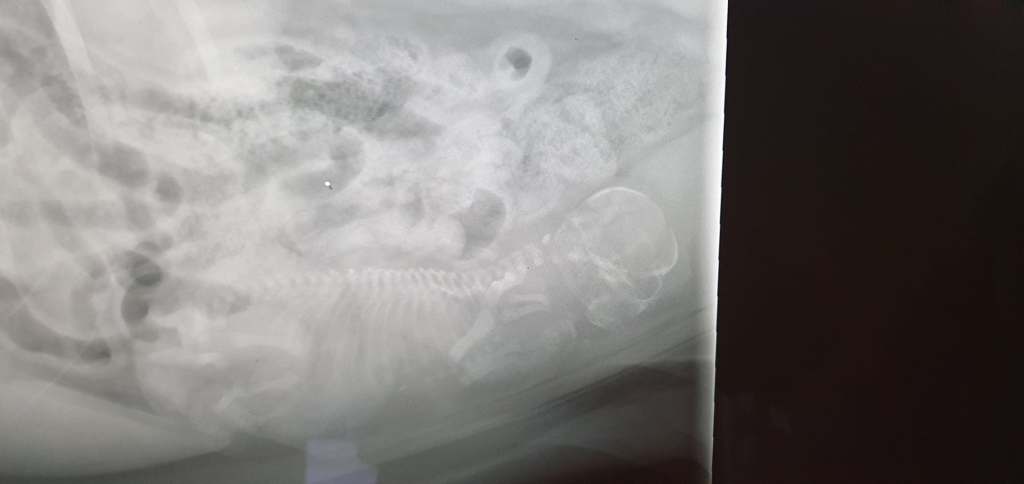

De weken daarna zien en merken we weinig aan Luna die stoïcijns doorgaat. Op 2 april bezoeken we de dierenarts opnieuw. We voelen de pup niet en er wordt een foto gemaakt. Op de foto is de pup duidelijk zichtbaar en we wachten gerustgesteld af.